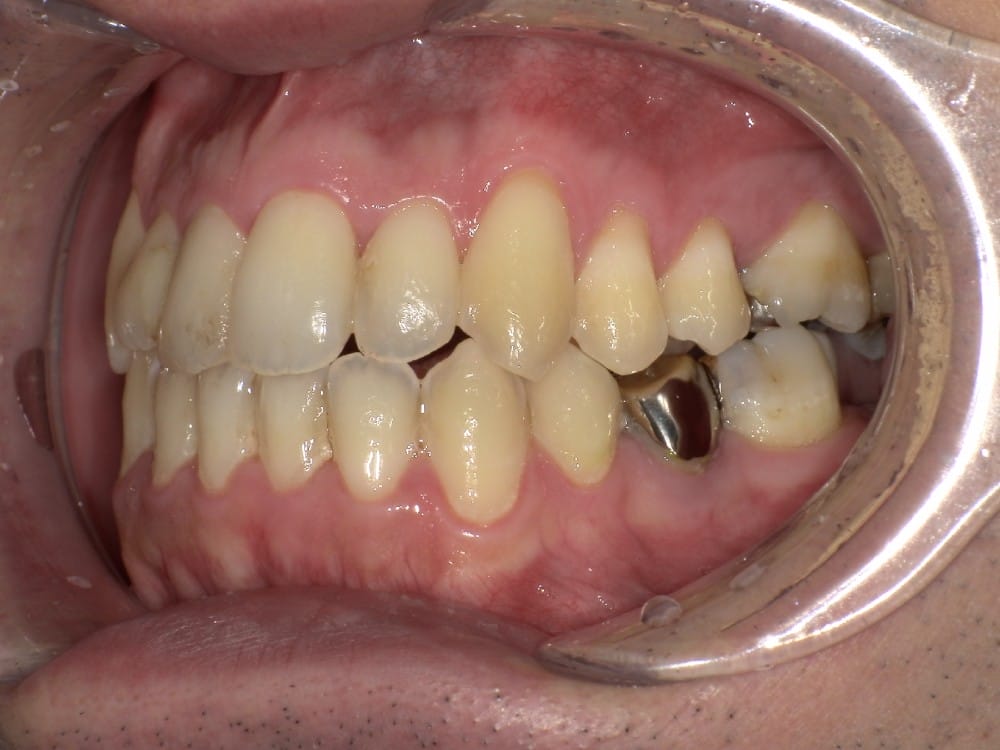

30代の女性で、受け口とガタガタを主訴にご来院されました。

治療前

分析しますと

- 骨格的な上下あごの前後差は中等度〜重度

- 噛み合わせの位置も下あごの奥歯が半分くらい前にズレていた

- 上の前歯が内側に傾斜している

というケースで、外科的な処置も検討するようなケースでした。

骨格的なズレや奥歯の噛み合わせのズレもあり、重度の受け口でしたが、上あごの前歯が内側に傾斜しているため、本来の歯の軸に戻すことで、受け口を改善できると診断し、治療を開始しました。

先ほどのケースと同じように、患者さまに外科的な手術の選択肢も提示しましたが、希望されず、横顔の変化はおそらく起こらないことを納得の上、治療をスタートいたしました。

今回のケースも奥歯の移動量が大きいため、マウスピースだけでは難しいと判断し、カリエールとよばれる装置を補助的に使用し、上下の噛み合わせの前後関係を整えることで、手術を行わずに機能面と見た目の両方が改善することにしました。

治療中の直近の写真です。生まれつき小さな歯である前から両側の2番目の歯は、被せ物をして見た目の回復をする予定にしています。

<治療前と現在の比較です>

矯正治療によって前歯の被さりを改善することで、先ほどの症例ほどではありませんが、下唇の突出感が減り、上唇も正常な位置に戻り、横顔がやわらかい印象に変化しました。